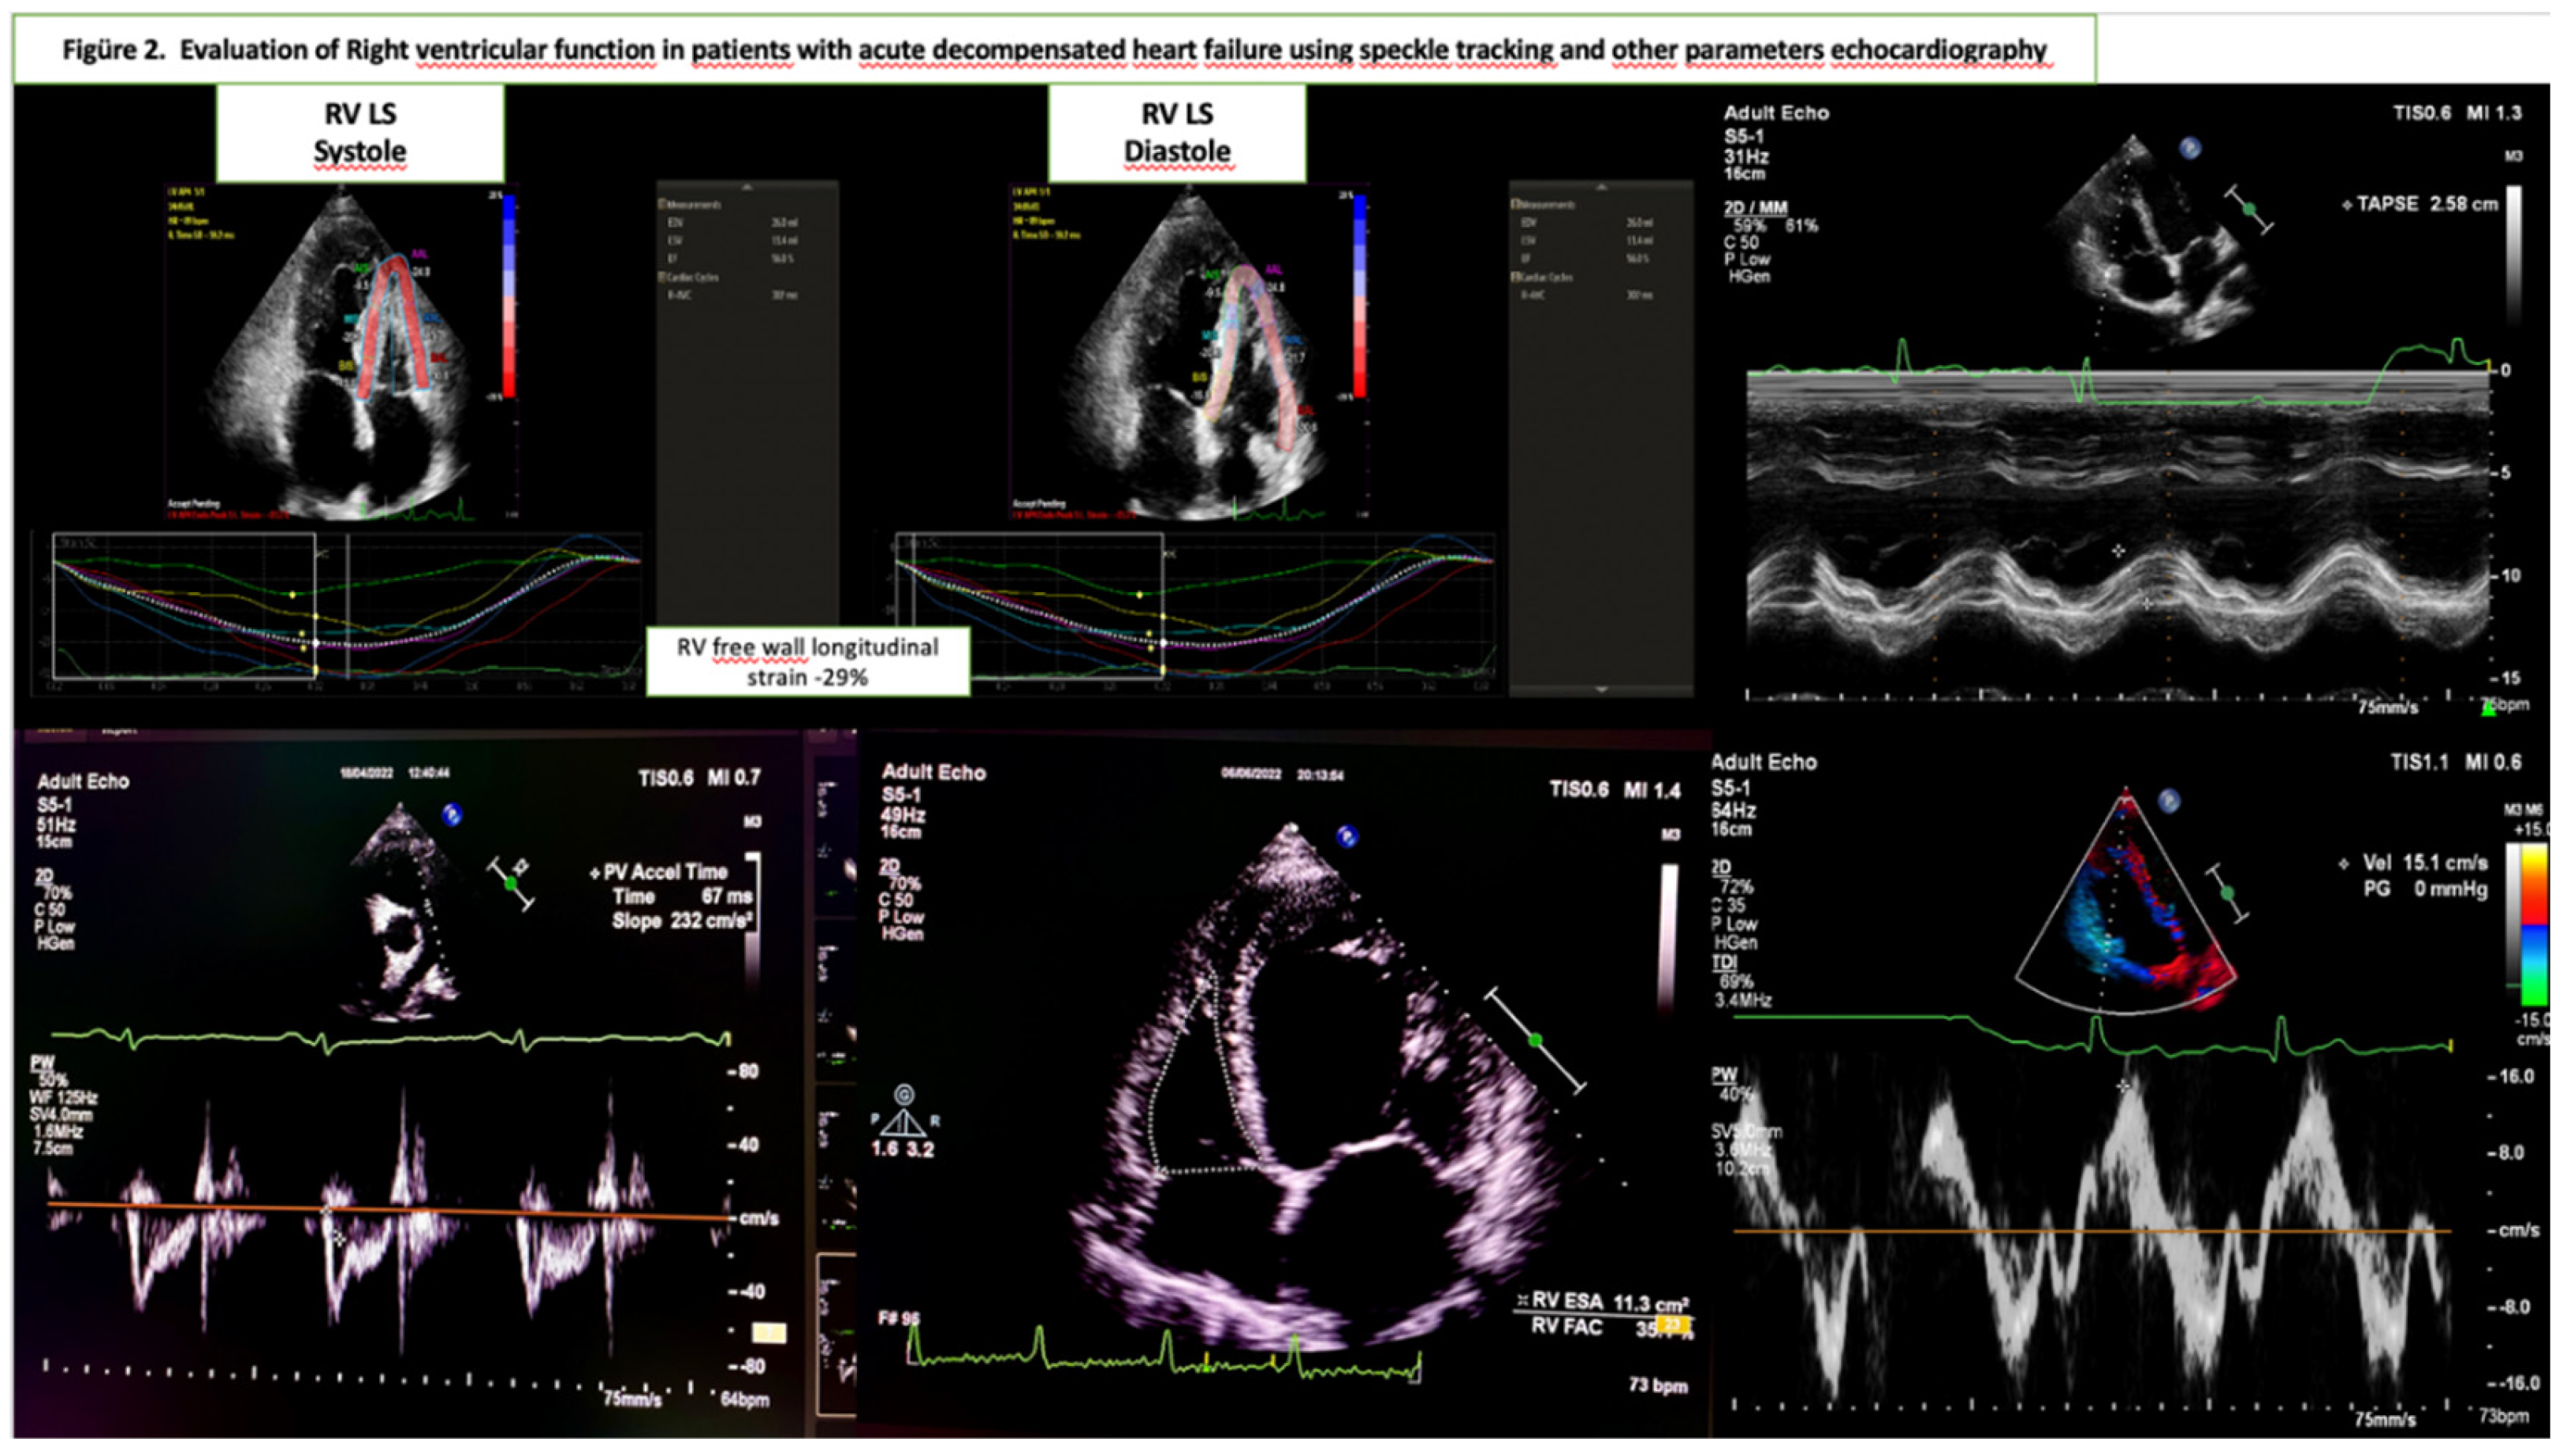

The parameters used for RV function evaluation in this study are reported in Figure 2. [14]

RV systolic function: Evaluated using the apical four-chamber view. The key parameters were as follows:

• Tricuspid annular plane systolic excursion (TAPSE) measured via M-mode.

• Peak systolic tricuspid annular velocity (RV TDI S′) was obtained using tissue Doppler imaging.

• RV fractional area change (RV FAC) was calculated as the percentage of RV end-diastolic and end-systolic area changes.

• Systolic pulmonary artery pressure was estimated using the peak velocity gradient of tricuspid regurgitation flow, right atrial pressure derived from the inferior vena cava dimensions, and respiratory variability.

Two-dimensional strain imaging was used to assess myocardial deformation as an early marker of RV systolic dysfunction. The time of aortic valve closure was considered end-systole, whereas the R-wave peak on the electrocardiogram was considered end-diastole. For strain measurements, an apical four-chamber view of the RV was captured, ensuring that all RV segments and the LV apex were within the imaging frame [14,15].

Boundaries of the endocardium, myocardium, and epicardium were automatically defined and manually adjusted to avoid errors. Analysis was performed using QLAB-CMQ software on the Philips Epiq 7C system. The RV free wall was divided into three segments (basal, mid, and apical) and the mean longitudinal strain was calculated across these segments. Patients with incomplete imaging windows or unmeasurable strain values were excluded.